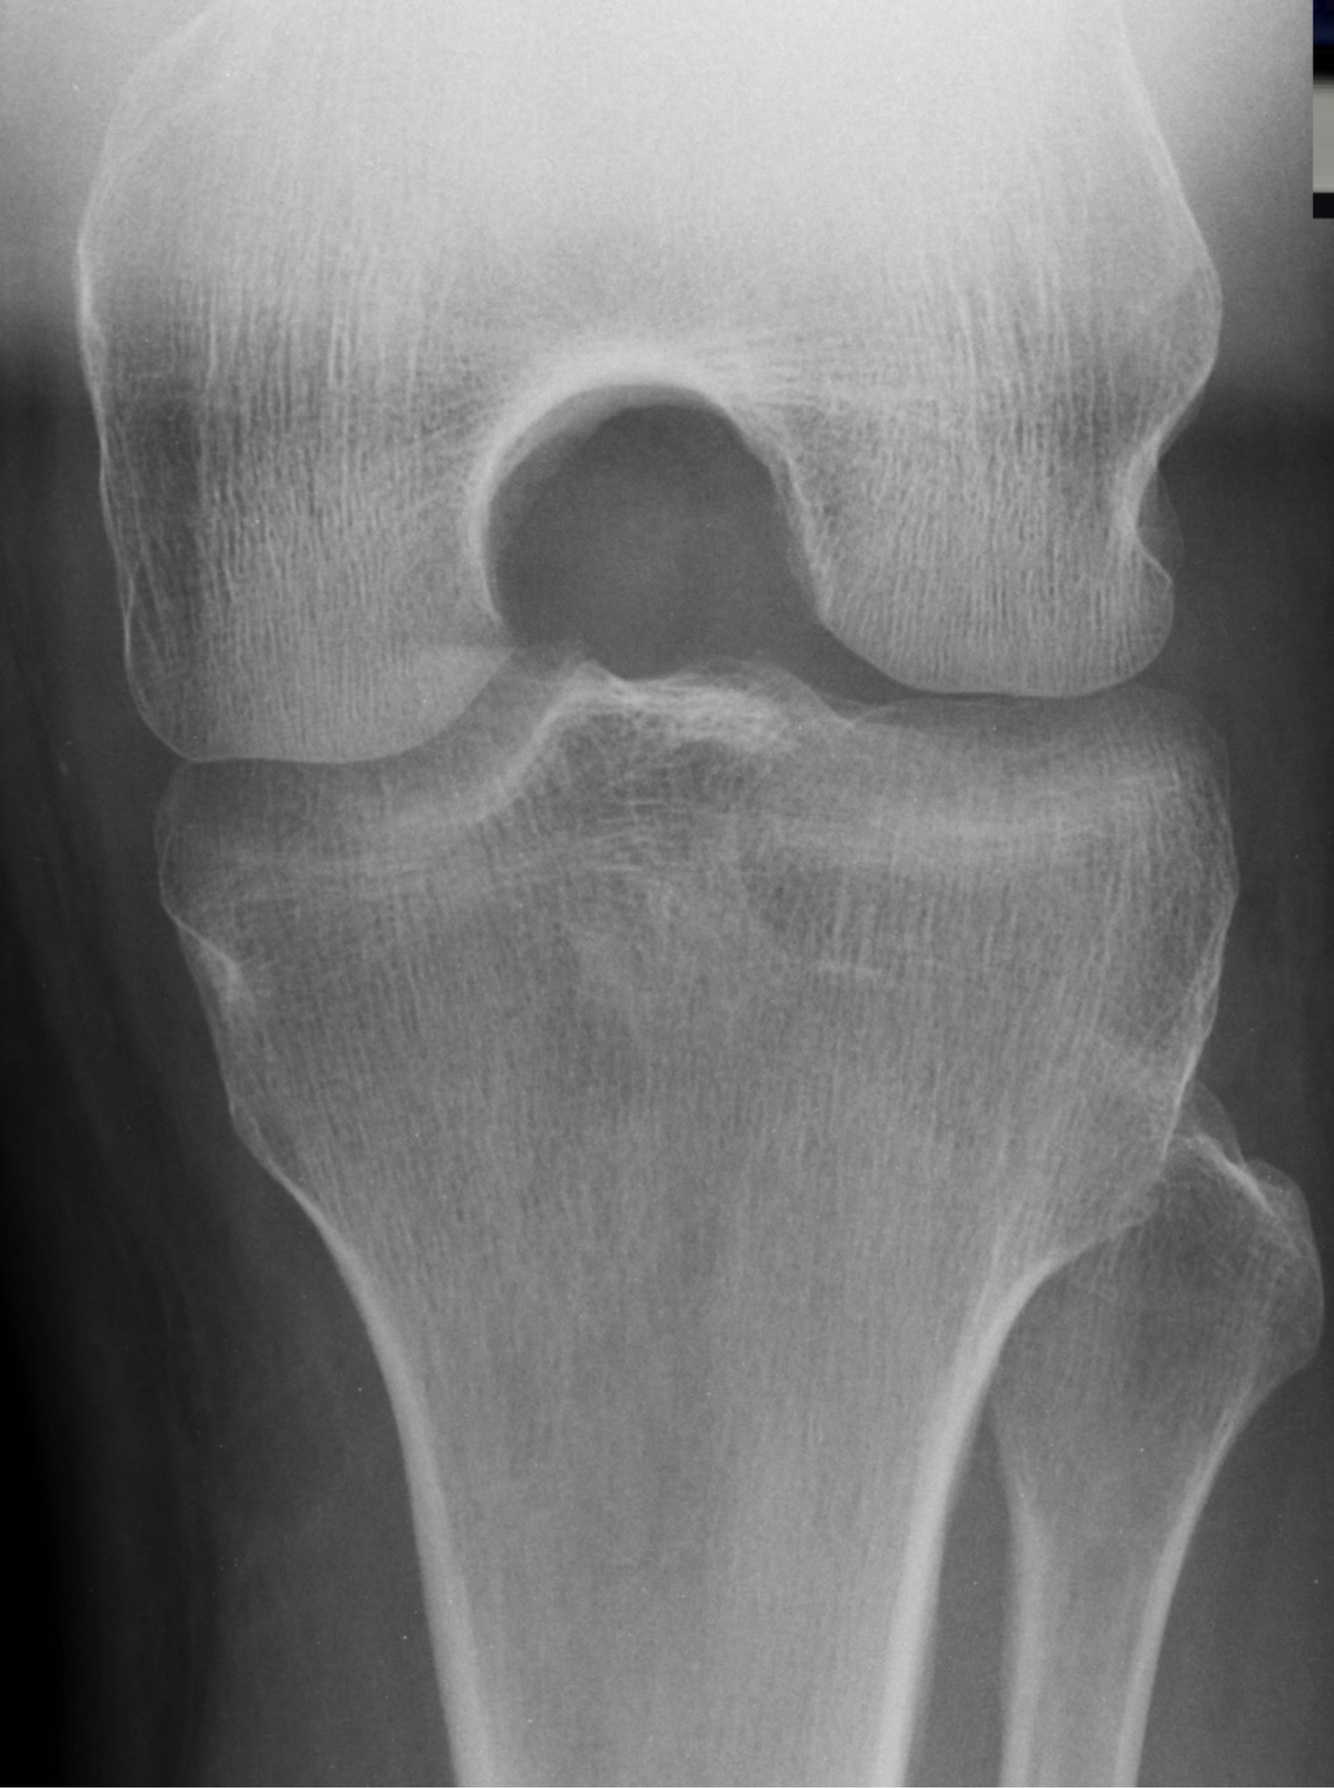

Qui suis-je?

Fracture de Segond 🦓

• Fracture avulsive en latéral du tibia sous le plateau tibial

• Hautement associée avec une déchirure du LCA, des ménisques, des structures postérieures du genou et de la capsule LAT

• Stress en varus et rotation tibiale INT